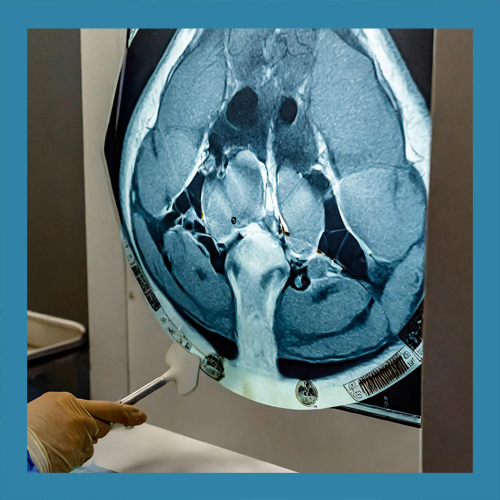

• 파열 정도에 따른 치료법의 차이

반월상 연골 파열의 치료는 손상의 위치와 정도에 따라 다르게 접근해야 합니다. 경미한 파열은 보존적 치료로 충분히 회복될 수 있지만, 심각한 경우에는 수술이 필요할 수 있습니다. 이를 정확히 판단하기 위해 MRI와 같은 정밀 검사가 필수적입니다.